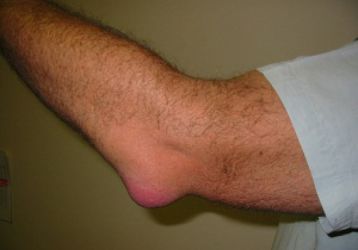

Артрит локтевого сустава: симптомы и лечение медикаментами и при помощи операций

Как развивается артрит локтевого сустава, на что нужно обратить внимание, существующие методы лечения и профилактики заболевания